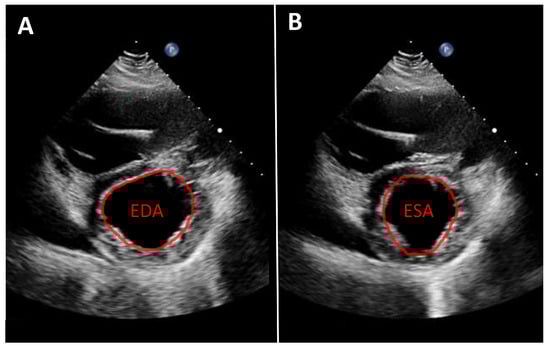

Quantifying aortic regurgitation (AR) in patients supported by a left ventricular assist device (LVAD) remains challenging. Conventional echocardiographic parameters are based on the assumption of isolated diastolic regurgitation, an assumption that often does not apply in the LVAD setting. In fact, holocyclic regurgitation (systolic and diastolic) is frequently observed, particularly in patients with more advanced AR (Figure 2).

Figure 2.

Patient with an LVAD and significant aortic regurgitation. Left: parasternal long-axis view. Right: M-mode of the aortic valve. M-mode color Doppler imaging clearly demonstrates both systolic and diastolic regurgitation.